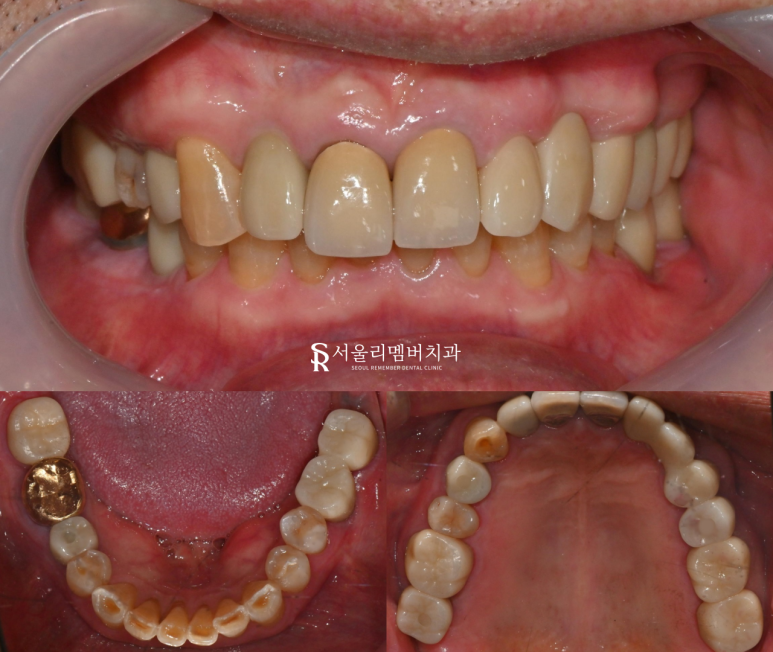

보철 수복

흔들리거나 치조골이 녹았던 이는

모두 발거하고,

인공치근을 심어 자연치를

대체해 준 모습입니다.

상부 보철을 지르코니아로 제작했기에

심미성이 매우 뛰어나고,

강도와 내구성도 강한

좋은 재료로 만듭니다.

치료기간 : 2024. 06. 15 ~ 2025. 01. 13